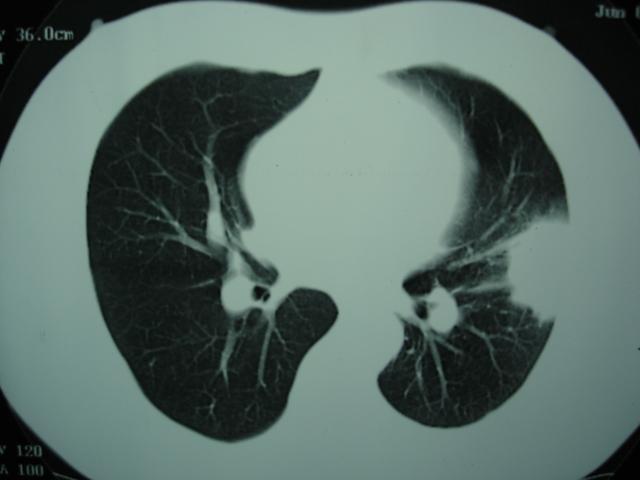

2009.6.4 2009.6.7 2009.8.21

第三次ct2009.8.21

病灶与胸膜成直边征,考虑炎症假瘤可能性大。

炎症,最厚一次已吸收

考虑左肺上叶炎症感染(炎性假瘤可能)。